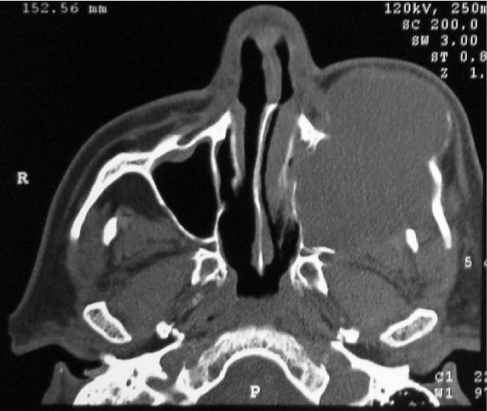

On aspiration biopsy was obtained by easily obtaining a light brown coloring liquid with blood residues. Under local anesthesia, incisional biopsy was performed for histopathological study, which later reported the antralpseudocyst, and its surgical enucleation was scheduled. Complementary imaging studies were carried out, which showed a radiolucent lesion in his tomographic image that occupies and destroys the left side of the jaw, including the floor of the orbit (Figure 2). A stereolithographic model was developed for the planning of the procedure (Figure 3).